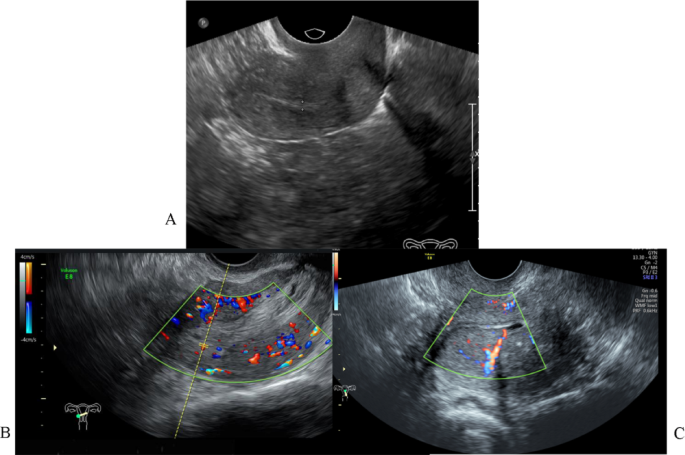

Ultrasonographic evaluation in postmenopausal women initially revealed normal endometrial morphology, characterized by a thin, homogeneous endometrium (< 4 mm in thickness) (Fig. 1A). Subsequent differentiation of malignant lesions was based on pathological features including endometrial thickening (≥ 4 mm), heterogeneous echogenicity, and myometrial invasion (Fig. 1B,C), which correlated with prominent vascular signals on Doppler imaging. When combined with elevated D-dimer levels, these sonographic parameters demonstrated superior diagnostic accuracy (AUC = 0.920, 95% CI 0.87–0.96) compared to individual biomarkers (D-dimer AUC = 0.710; abnormal bleeding AUC = 0.781).

Transvaginal ultrasonographic features of normal endometrium and endometrial carcinoma. (A) Normal postmenopausal endometrium showing a thin, homogeneous endometrial line with well-defined borders and no detectable blood flow. (B) Endometrial carcinoma displaying abnormal thickening with heterogeneous echogenicity. Color Doppler imaging demonstrates increased vascularity with multiple areas of blood flow signals (red and blue areas) within the endometrial tissue. (C) Advanced endometrial carcinoma with irregular borders and myometrial invasion. Note the disruption of the endometrial–myometrial junction and the presence of blood flow signals extending into the superficial myometrium.